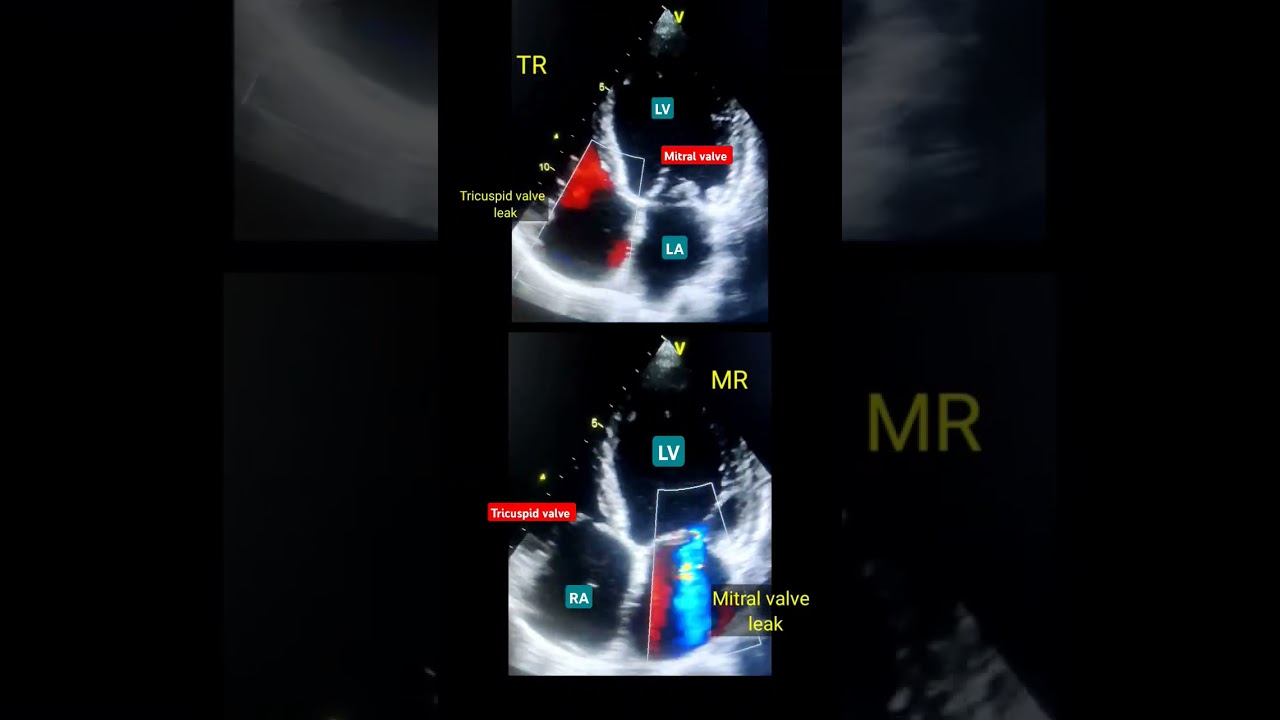

MR, TR ( valve Leak ) Echo l वाल्व इको

echo test of heartecg testTMT testAngiographyAngioplasty of LAdweak Heart treatmenthow echo identify heart blockageheart anatomyheart soundhole in heartecho test kaise krte hAngiography kaise krte h100% heart blockage treatmenttest for heart blockageheart blockage ka kaise pta kremedical knowledgebiology classejection fraction of heartmitral valve leak echotricuspid valve echo

MR, TR ( valve Leak ) Echo l वाल्व इको #echo #shorts